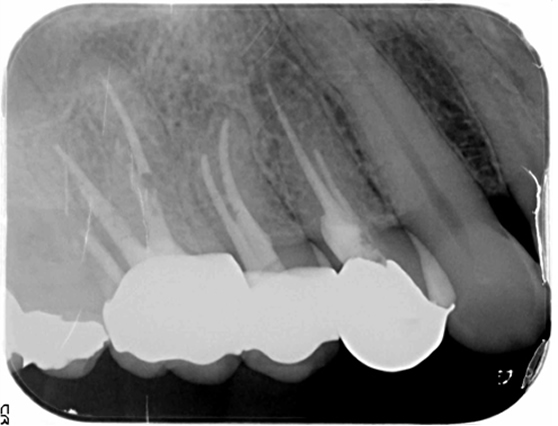

意図的再植術

意図的再植術は、歯根の先端に感染源がある場合、一度、歯を抜いてから感染源を切り取りし、再び歯を戻す治療法です。歯根端切除術と同様の治療目的ですが、歯根端切除術が適応外の部位に行います。